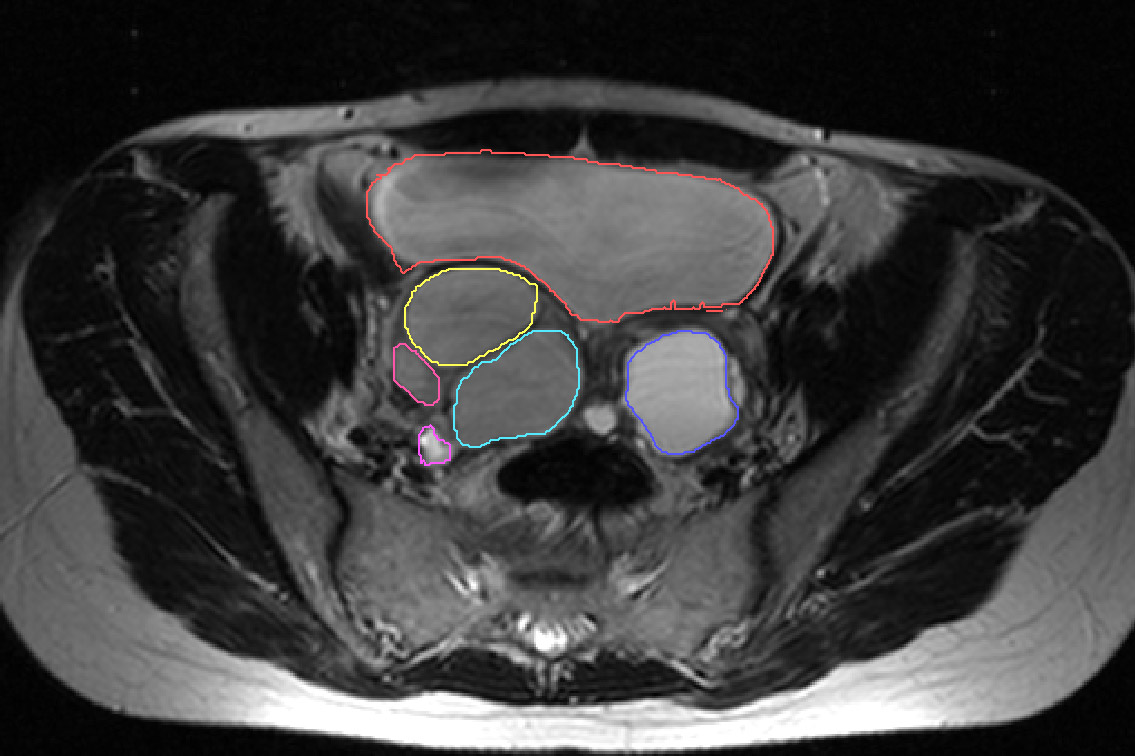

Étude en cours sur les kystes ovariens avec le Centre national de recherche médicale Almazov (Saint-Pétersbourg).

Quelques images